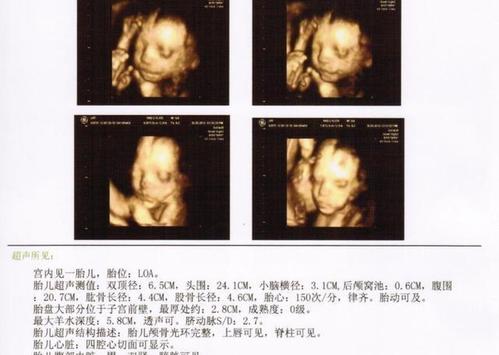

确认男宝四维图,四维单子上女孩标志

怀孕26周, 四维确认男宝一枚, 给大家分享症状吧

四维一次性通过!男宝一枚!

确定男宝一枚,之前发的四维单有猜对的